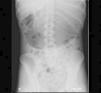

Paciente de 16 años que consultó en nuestro hospital por dolor epigástrico tras ingesta alimentaria de gran entidad realizada 8 horas antes. Refirió incapacidad para el vómito e indicó que había sido vista en otro centro donde se recomendó reposo digestivo y dieta blanda. Diagnosticada de bulimia nerviosa no restrictiva en tratamiento farmacológico (bromazepam, topiramato y fluoxetina) con control parcial de la sintomatología había presentado episodios previos semejantes pero logrando el vómito posteriormente. No asociaba otros antecedentes personales o familiares de interés. La paciente mostraba gran agitación, inquietud e indicaba dolor abdominal generalizado. En la exploración física se objetivó distensión abdominal con defensa voluntaria a la palpación. No presentaba alteraciones en la frecuencia cardiaca o tensión arterial con bioquímica sanguínea y gasometría venosa normales (ph 7,37 con ácido láctico de 0,5mmol/l). Ante la sospecha de dilatación gástrica se decidió introducir una sonda por vía nasogástrica extrayéndose 700ml de contenido estomacal. Posteriormente se solicitó una radiografía de abdomen que demostró una gran dilatación gástrica con el límite inferior del estómago en la región pélvica (fig. 1). Se decidió ingreso en la unidad de cuidados intensivos, para observación continua, ante el riesgo de rotura gástrica. Se mantuvo a dieta absoluta durante 48h y recibió fluidoterapia según necesidades basales. Se inició tratamiento procinético y protector de la mucosa estomacal. Durante su permanencia en la UCI se mantuvo la sonda nasogástrica abierta para continuar el vaciamiento gástrico. Tras control radiológico (fig. 2), y dada la ausencia de complicaciones, se reinició la alimentación oral progresiva sin incidencias. Posteriormente, recibió el alta bajo control de servicio de psiquiatría.

El diagnóstico de imagen se fundamenta en la radiografía de abdomen permitiendo esta una valoración aproximada de la dilatación gástrica. En aquellos casos en los que no existan antecedentes de pérdida de peso, enlentecimiento del vaciado gástrico, atracones alimenticios o fenómenos obstructivos conocidos puede ser necesaria la realización de una tomografía computarizada abdominal con el objeto de descartar anomalías anatómicas o procesos intercurrentes desencadenantes de DGA1.